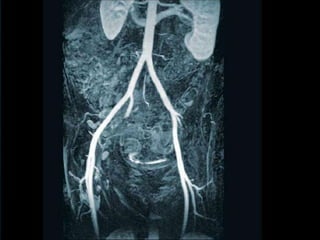

RECONSTRUÇÃO EM 3 DIMENSÕES.

APLICAÇÕES CLÍNICAS